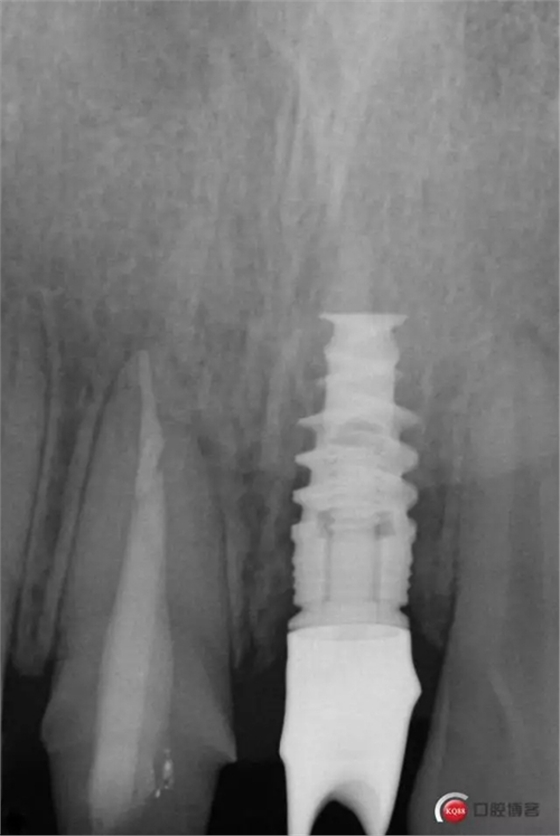

種植后修復,我們要把握每一個細節(jié),比色,轉(zhuǎn)移桿的就位,我們必須把臨床做好,技工師傅才會給我們做出好的修復體,減少一些不必要的失誤,首先術前的檢查是必要一步 ,再是器械的準備使我們臨床操作有條不紊,術前拍照,o-bite取咬合記錄,消毒修復術區(qū),旋出愈合基臺,生理鹽水沖洗袖口,拍照袖口,安放合適轉(zhuǎn)移桿,拍X線見轉(zhuǎn)移桿就為良好,硅橡膠取模,術后旋回愈合基臺,拍照比色。

藻酸鹽對頜取模,超硬石膏灌注。發(fā)加工廠,與技工溝通注意事項,等修復體做好后,檢查模型。是否就位,是否密合,預約患者復診戴牙,消毒修復區(qū),旋出愈合基臺,定位器指導安放修復基臺,試戴冠,調(diào)磨鄰接及 咬合至合適,拋光,患者滿意,加力扳手加力至30N,拍X片見就位良好,特芙蓉及暫封膏封中央螺絲孔,聚羧酸鋅粘固劑粘固,或是樹脂水門汀粘固,清理多余粘結(jié)劑,光固化樹脂封螺絲孔,拋光。術后注意隨訪。